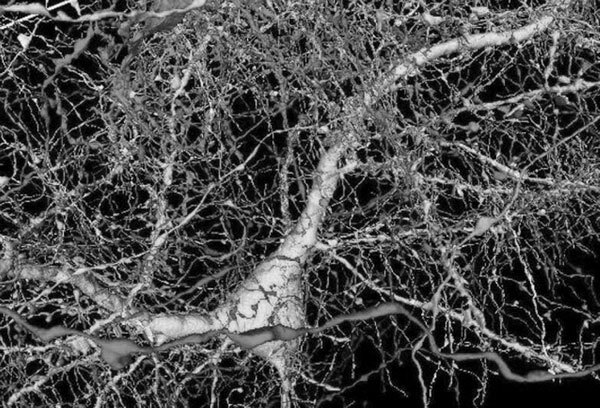

Вот так врачи пытались вылечить больных с помощью электрического тока, а заодно случайно нашли способ искусственно вызвать такое неординарное, но вполне конкретное чувство, как «стойкость перед лицом беды». Ниже вы можете ознакомиться со снимком МРТ, где отмечены места размещения электродов, подача тока на которые вызывала описанное чувство.

Анатомическое расположение внутричерепных электродов, вызывающих чувство «стойкости перед лицом беды»

На иллюстрации очень упрощенный вариант такого соединения. На самом деле здесь должно быть нарисовано ~ 90 миллиардов таких кружков и порядка 100 триллионов связей. Представить, как это выглядит в реальности, поможет очень хорошая визуализация, которую команда исследователей из «Гугл Ресерч» выложила в общественный доступ в 2021 году. Чтобы получить ее, ученые пропитали смолой один кубический миллиметр мозговой ткани, а после нарезали ее на слои толщиной 30 нанометров – это в тысячу раз тоньше человеческого волоса – и просканировали каждый слой электронным микроскопом. Из полученных данных собрали трехмерную модель, которая теперь доступна каждому желающему на нее взглянуть. Несмотря на то что представлена карта лишь мизерного участка мозга, даже она настолько огромна, что сами создатели не смогли изучить ее полностью.

Это фрагмент той модели, на нем запечатлен всего лишь 1 нейрон и около 4000 подходящих к нему нервных контактов. Соедините между собой 86 миллиардов таких фрагментов, и вы получите примерную карту мозга.